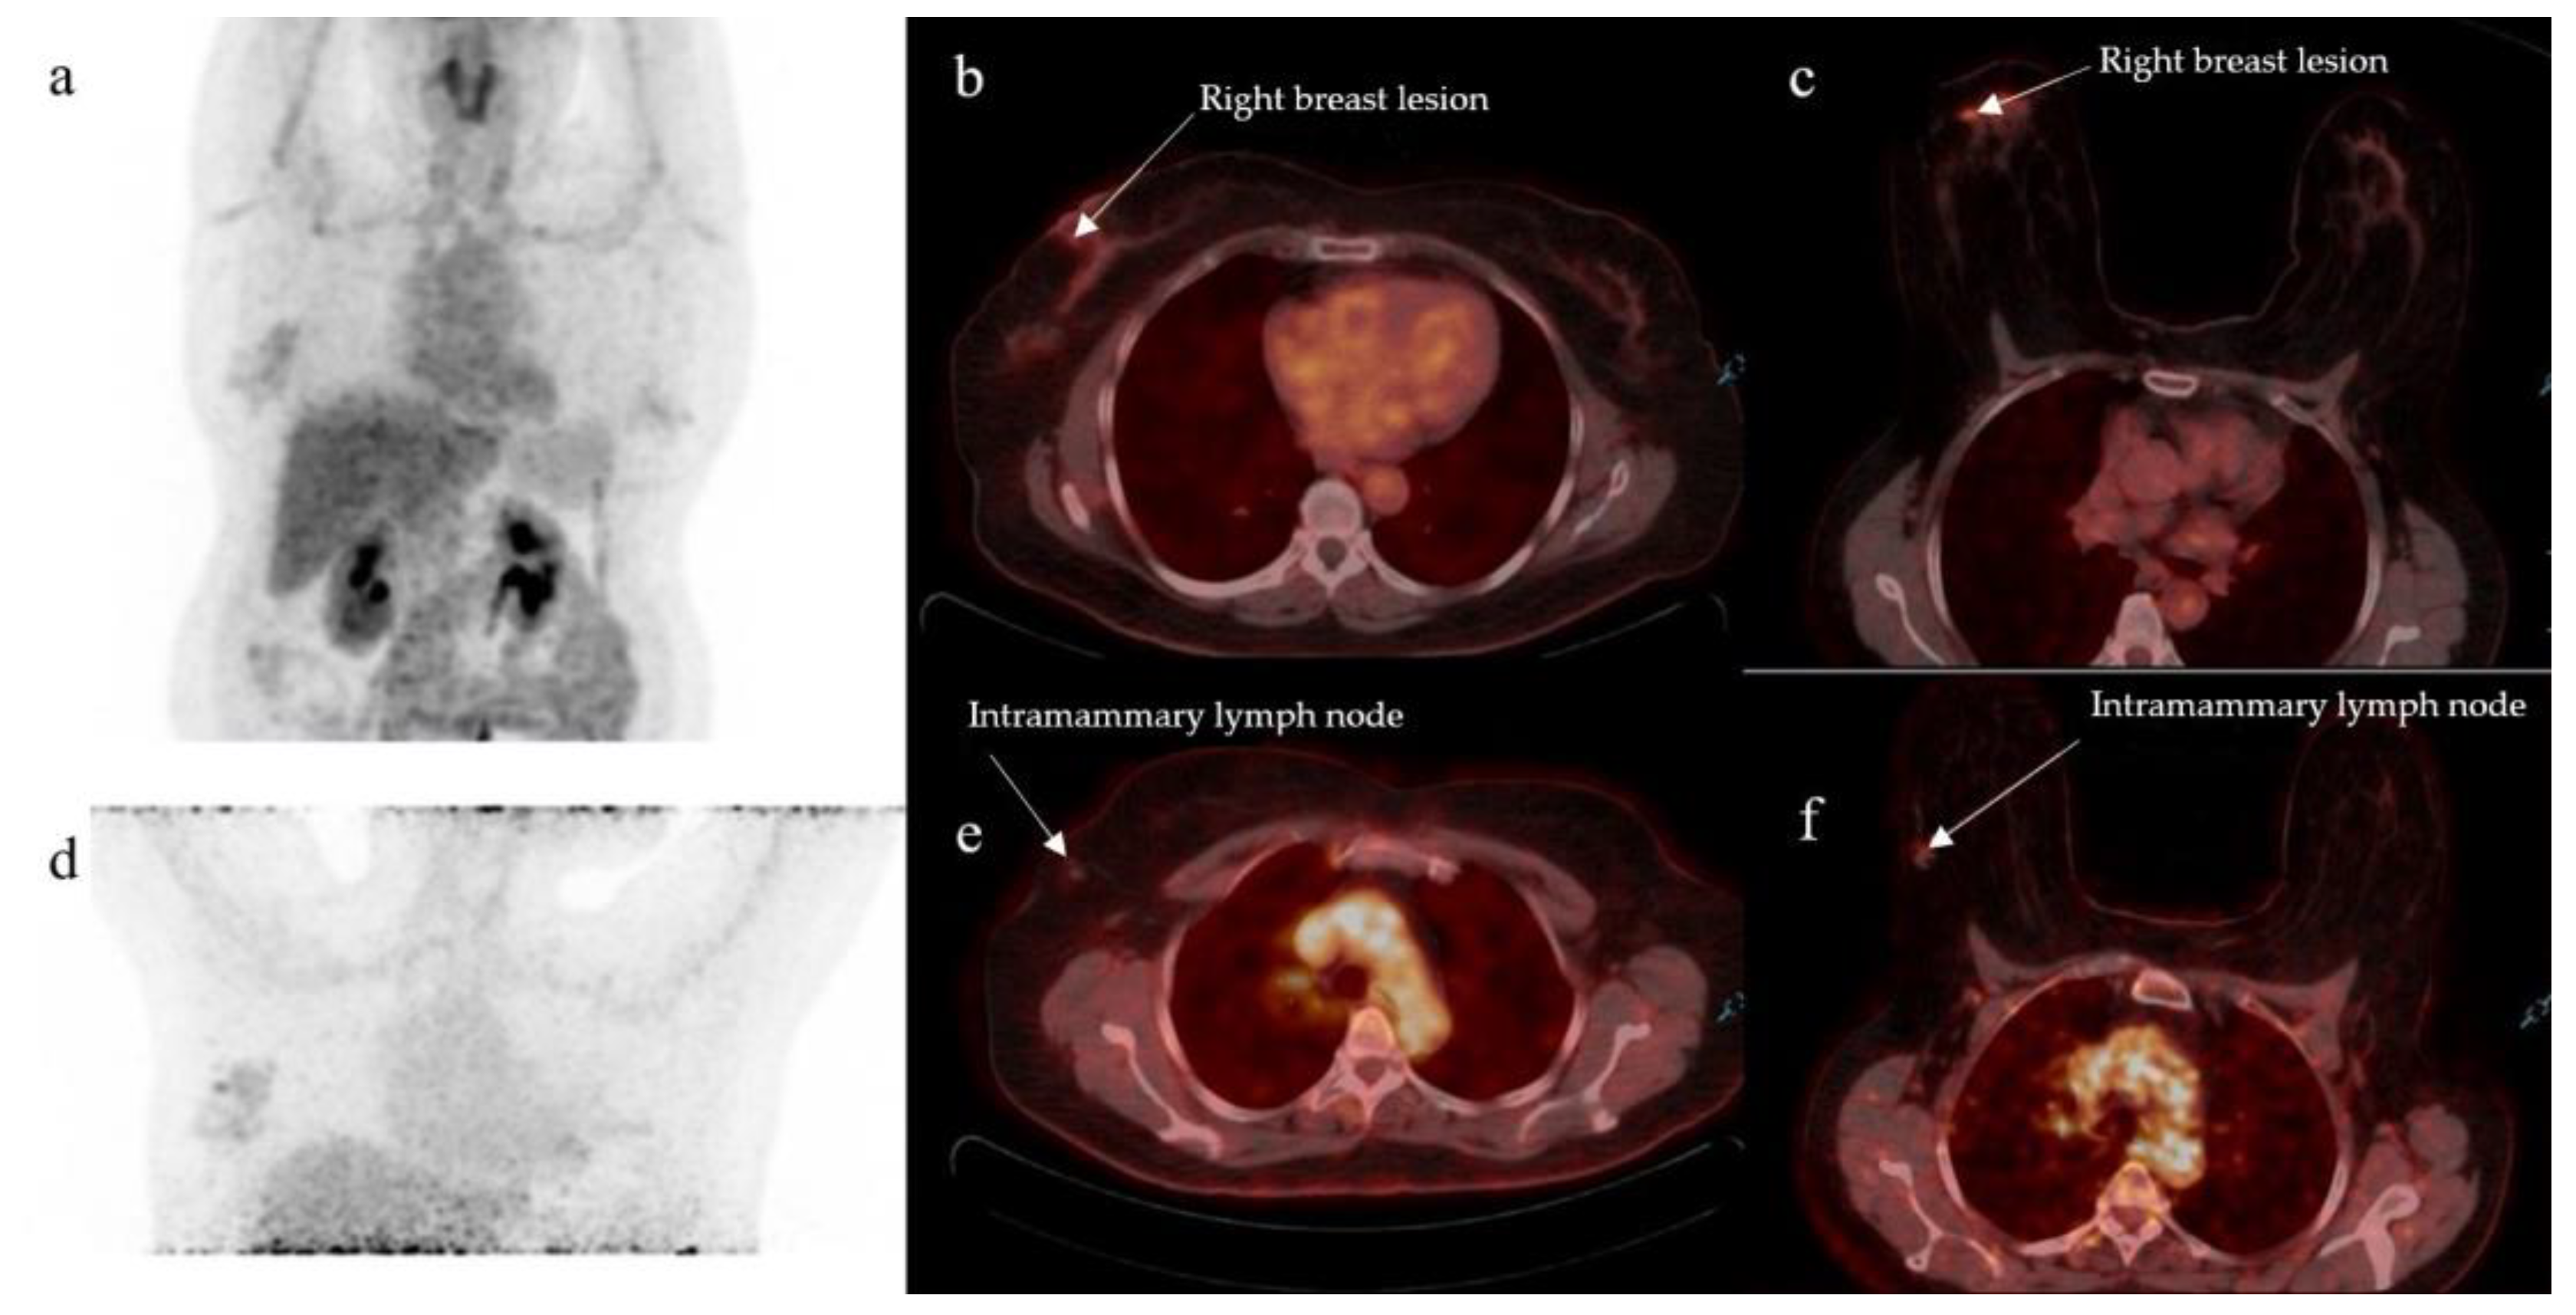

- On supine position acquisition, primary breast lesions were missed in three patients, all of which were detected on prone position. One such example is seen in Figure 2,

- A single lesion was detected on supine position in two patients who, on prone position, each had two lesions detected (Table 1),

- One lesion was detected on supine position in a patient who was found to have three lesions on prone acquisition (Table 1).